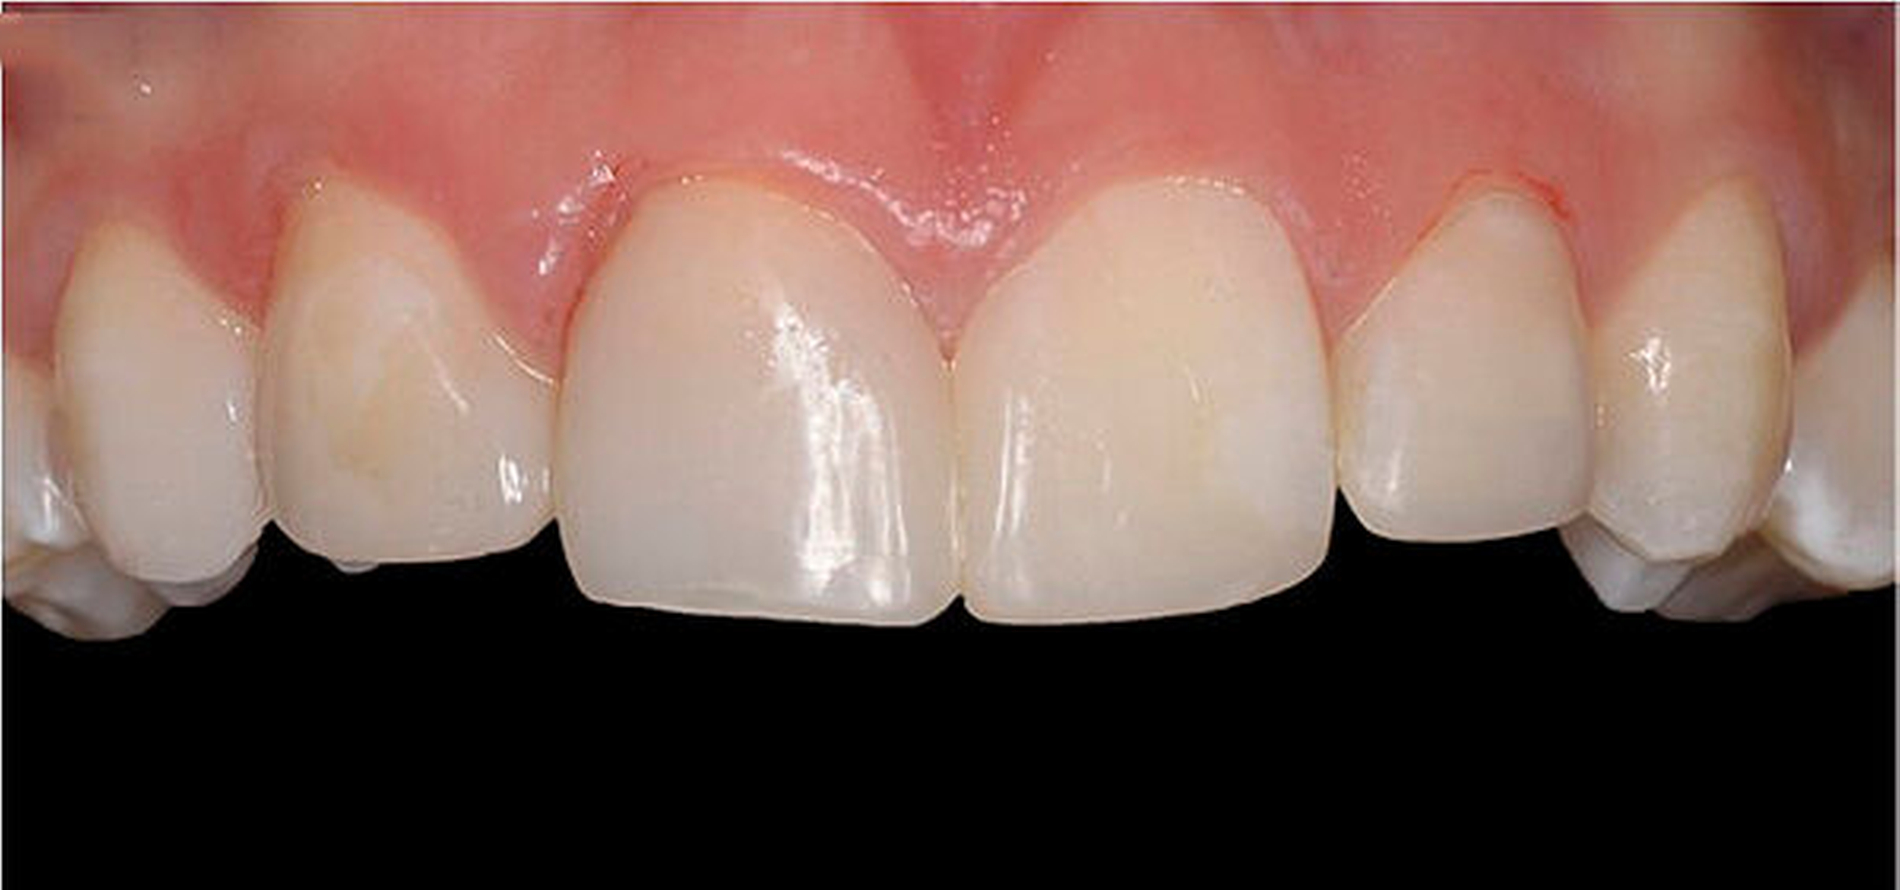

Die Rekonstruktion von Zähnen mit Komposit ermöglicht eine direkte und maximal zahnerhaltende Therapie, bei der die Zahnhartsubstanz nicht oder nur minimal im Sinne einer Anschrägung abgetragen werden muss. Im Vergleich zur Rekonstruktion mit keramischen Veneers muss dabei in der Regel wesentlich mehr Zahnhartsubstanz geopfert werden, um die nötigen Keramikschichtstärken einhalten zu können. Reparaturen, Farb- und Formanpassungen lassen sich mit der Komposittechnik im Vergleich zu Keramikrestaurationen immer wieder anpassen. Insbesondere bei jungen Patienten im Wachstum ist dies von Vorteil, um bei Veränderungen der Gingivaverhältnisse die rekonstruierten Zähne ihren Nachbarzähnen anzupassen (Verschluss schwarzer Dreiecke, zervikale Ausformungen).